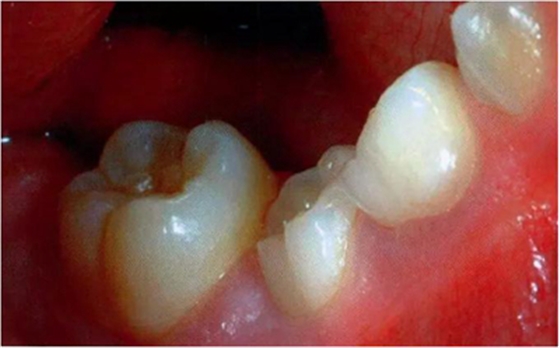

圖2:中度下沉的臨床像